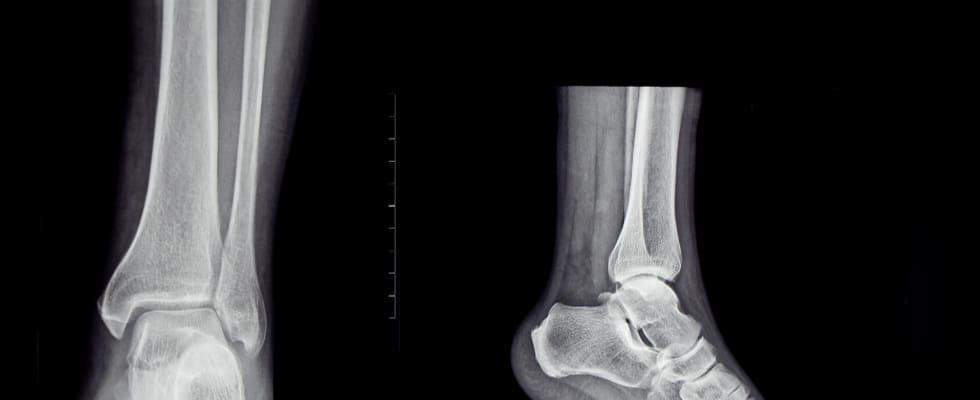

Radiografía de pie

La radiografía de pie es una técnica de diagnóstico por imagen que utiliza rayos X para obtener imágenes detalladas de los huesos y estructuras internas del pie. Este procedimiento es fundamental para identificar fracturas, deformidades, infecciones, artritis y otras condiciones que afectan la salud del pie. Al proporcionar una visión clara y precisa de la anatomía del pie, la radiografía permite a los profesionales de la salud realizar diagnósticos exactos y planificar tratamientos adecuados, mejorando así la calidad de vida del paciente.

Se utiliza para diagnosticar y evaluar diversas afecciones y lesiones en el pie y el tobillo. Este procedimiento permite identificar fracturas, esguinces, dislocaciones, infecciones, artritis y otras patologías óseas. Además, se emplea para detectar anomalías estructurales, como espolones óseos o deformidades congénitas. La radiografía de pie también es útil para planificar tratamientos quirúrgicos y monitorizar la recuperación postoperatoria. Gracias a su capacidad para proporcionar imágenes detalladas de los huesos y las articulaciones, se considera una herramienta esencial en la práctica médica ortopédica y podológica.

Se realiza utilizando una máquina de rayos X que emite una pequeña cantidad de radiación para capturar imágenes detalladas de los huesos y tejidos del pie. Durante el procedimiento, el paciente se coloca de pie o se sienta, y el pie se posiciona en diferentes ángulos para obtener las vistas necesarias. El técnico de radiología ajusta la máquina y toma las imágenes, las cuales son luego revisadas por un radiólogo. Este especialista interpreta las radiografías para identificar fracturas, deformidades, infecciones u otras condiciones médicas que puedan afectar el pie.